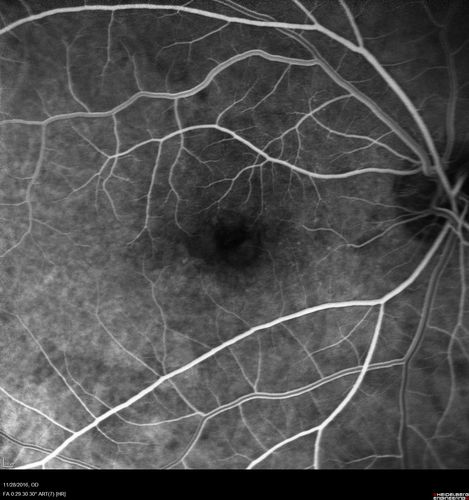

Confluent Soft Drusen with Subetinal Fluid - Right Eye

Asymptomatic 85 year old man.  OCT shows pocket of subfoveal fluid in the center of the macula.  This could be mechanical from the drusen preventing the retina from settling down.  Testing did not reveal a CNVM and subsequent OCT 6 weeks later showed no change in structure.